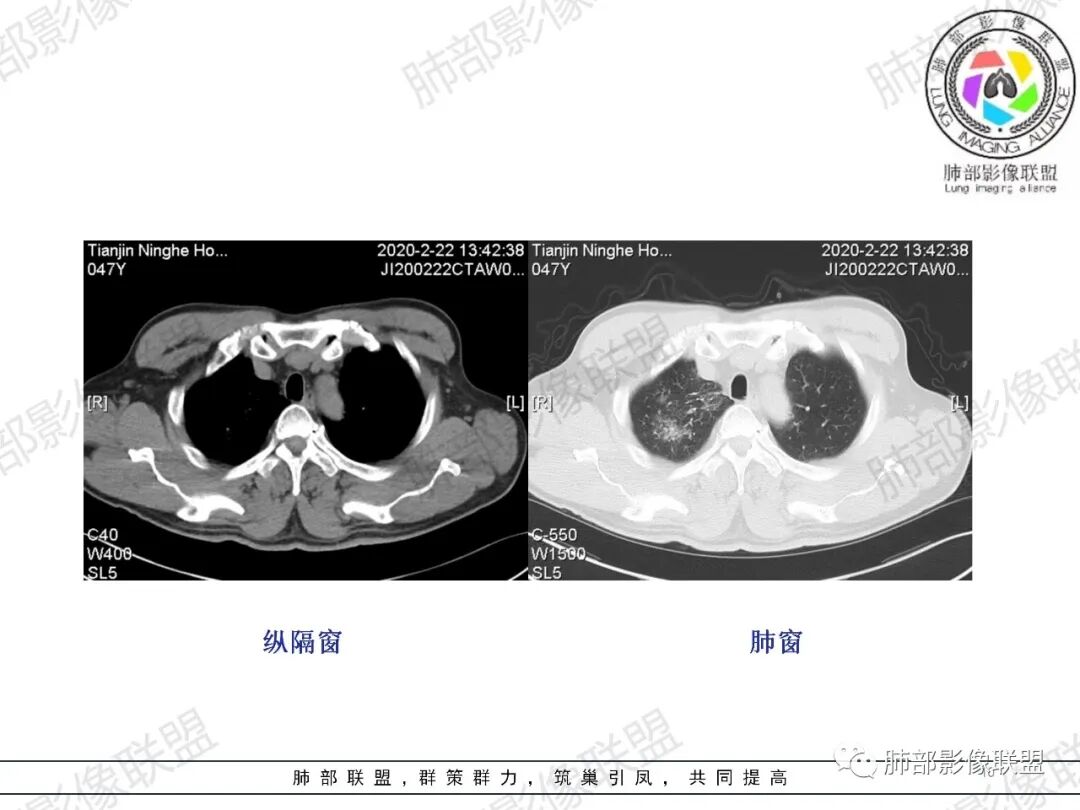

张延军:右肺上叶多发大小不等结节,部分界清,反晕征(+),下叶胸膜下磨玻璃影,纵膈窗似较对称血管细,结合咳血症状,考虑栓塞

小锁:中年男性患者,急性起病,胸闷气喘伴有胸痛,低热,低氧,白细胞增高。CT:右肺上叶斑片状稍高密度影,粟粒样树芽征,有钙化,考虑继发性结核;右肺下叶肺动脉增粗,溶冰征,提示血管来源病变,结合临床病史,考虑肺栓塞。

CT肺动脉成像(CTPA)以其高度的敏感度和特异度,已经作为临床上诊断急性肺栓塞的首选方法。

中央型肺栓塞包括栓塞部位累及纵隔动脉(肺动脉干,左、右肺动脉,左、右叶间动脉)及肺叶动脉(双肺上叶肺动脉、右肺中叶及左肺舌叶肺动脉、双肺下叶肺动脉);周围型肺栓塞包括栓塞部位累及肺段及亚段动脉(肺段动脉包括双肺上叶3支、右肺中叶及左肺舌段各2支、双肺下叶各5支)。

急性肺栓塞患者CTPA上胸部继发改变包括肺动脉干增粗、右心增大、肺梗死、马赛克征、Westermark征、心包积液、胸腔积液、肺不张/肺膨胀不良等。

肺动脉高压的标准以肺动脉干直径大于3 cm或肺动脉干直径大于同层面升主动脉直径。右心增大的标准以横断位四腔心层面右心室内径与左心室内径比值大于1,或出现室间隔变直或凹陷等征象。

马赛克征反映了血管阻塞或通气不良。可能是由于中央组肺栓塞引起的血管阻塞及血流差异更为明显,继而导致肺血流分布不均。

Westermark征是指当肺叶或肺段动脉栓塞时,相应范围的肺纹理减少或消失,透亮度增高。